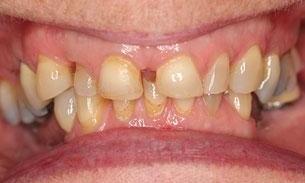

This gallery highlights the treatment of a patient who previously had braces but required additional restoration to close residual gaps. A Maryland cantilever bridge was placed to fill in these spaces, improving both dental function and aesthetics.